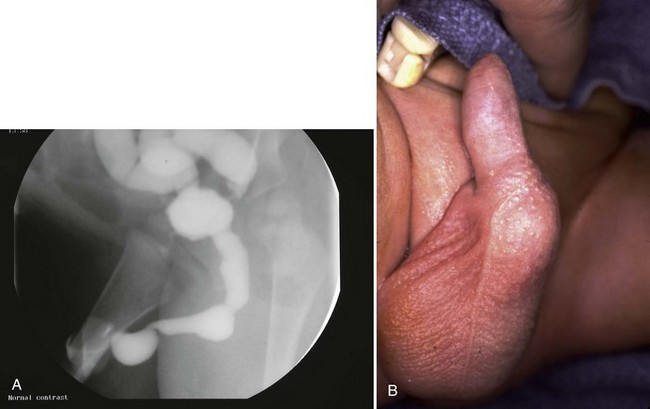

Young described type III valves as a membrane lying transversely across the urethra with a small perforation near its center (Fig. 126–3). The membrane is distal to the verumontanum and sometimes is elongated like a wind sock reaching the bulbous urethra (Field and Stephens, 1974). Type III valves make up only 5% of the total. Young described them as follows:

Figure 126–3 A, Voiding cystourethrogram demonstrates a typical type III posterior urethral valve with a transverse septum crossing the urethra at a right angle distal to the verumontanum. B, A cystoscopic image from the distal urethra shows the thin membrane and a small off-center opening.

The embryologic origin of type III valves has been attributed to incomplete dissolution of the urogenital portion of the cloacal membrane. Type III valves present in the same manner and are managed in the same way as the more common type I, although there is some evidence that type III valves have a worse prognosis (Rosenfeld et al, 1994).